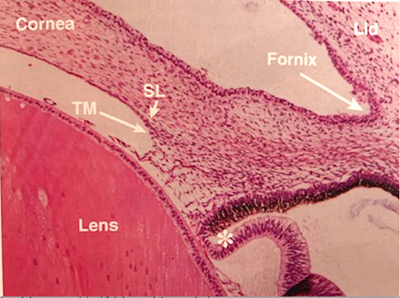

Microfotografía de un feto, mostrando un ángulo inmaduro (48 mm?). Se ve el fornix conjuntival y el párpado, la córnea, el cristalino, una incipiente cámara anterior. El ✻ muestra el margen de la copa óptica; SL es la Linea de Schwalbe y T.M el futuro Trabéculo.

T.M el futuro Trabéculo.- Tomada de Anatomy of the Eye and Orbit- The clinical Essentials- Thomas F.Freddo and Edward Chaum,.2018